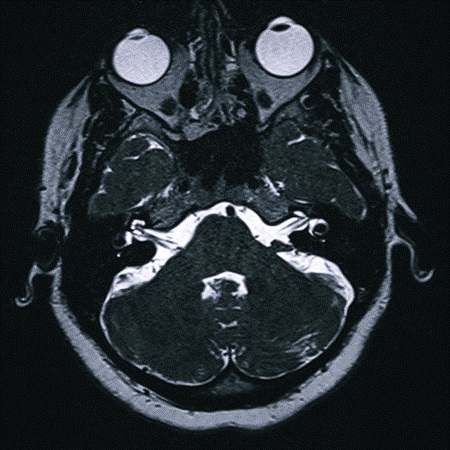

Для постановки диагноза опытному невропатологу достаточно внимательно выслушать, на что жалуется больной, и тщательно его осмотреть. Диагностика также требует точного выявления причины патологии. Для этого применяют МРТ. Она может обнаружить опухолевый процесс или склероз.

Важно выявить процесс на ранней стадии, установить его происхождение и отследить развитие.

Магнитно-резонансную томографию тройничного нерва назначают в качестве дополнительного метода обследования после общих анализов, проверки рефлексов, оценки проводимости. Поводом к МР-сканированию может стать неэффективность стандартной противовоспалительной терапии.

Диагностика воспаления тройничного нерва Для определения наличия опухолей в головном мозге используются МРТ и КТ. Также пациента могут направить на общий или биохимический анализ крови, рентген легких, УЗИ мягких тканей или офтальмоскопию.